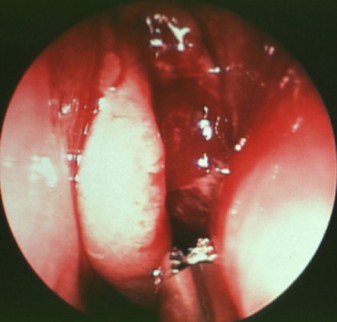

(鼻内窥镜下可见鼻腔息肉肿物、鼻甲肥大)

经过系统检查发现,扎西次仁的双下鼻甲充血肿大,鼻中隔右偏,鼻道内有息肉样性新生物增生,双侧鼻通气欠佳,双测扁桃体肿大充血,根据以上检查结果,扎西次仁的以往病史,医生给出的诊断结果是:扎西次仁并非只是单纯的鼻息肉,他同时患有双侧鼻腔息肉,慢性鼻窦炎,慢性鼻炎以及慢性扁桃体炎。

由几位医生对其进行了专项会诊,很快制定出了详细的手术方案。手术由院长亲自主刀,在鼻内镜下进行了双侧鼻腔息肉摘除术、双上颌窦口扩大、双侧筛窦开放以及双下鼻甲部分切除术,解决了扎西次仁的鼻腔中存在的问题。